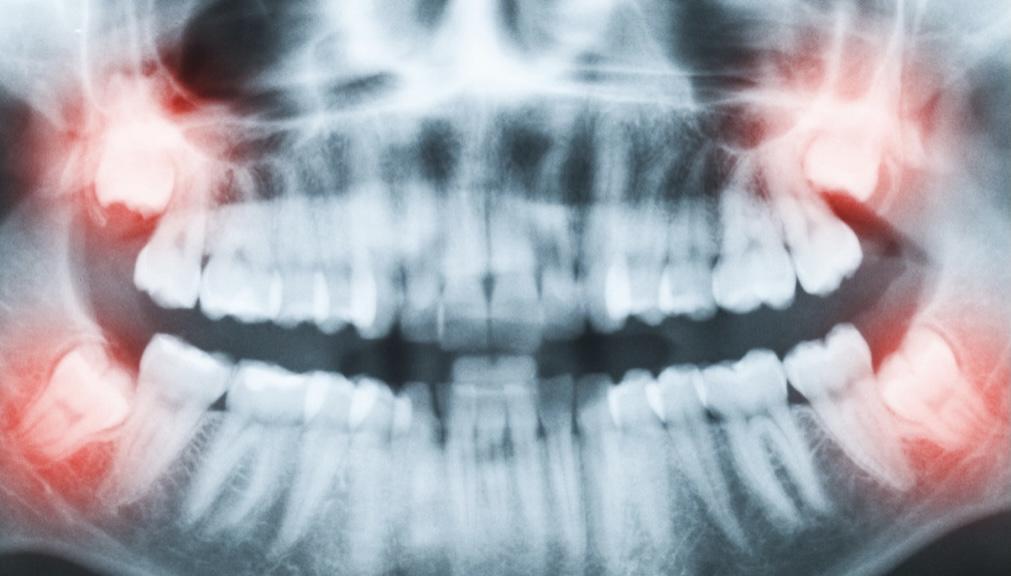

假如吃了止痛藥還是果不,甚至出現(xiàn)了拔牙一側(cè)頭疼,那么有可能出現(xiàn)了干槽癥,應(yīng)該及時(shí)找醫(yī)生進(jìn)行復(fù)診。

(面部腫脹、疼痛嚴(yán)重者隨時(shí)復(fù)診)